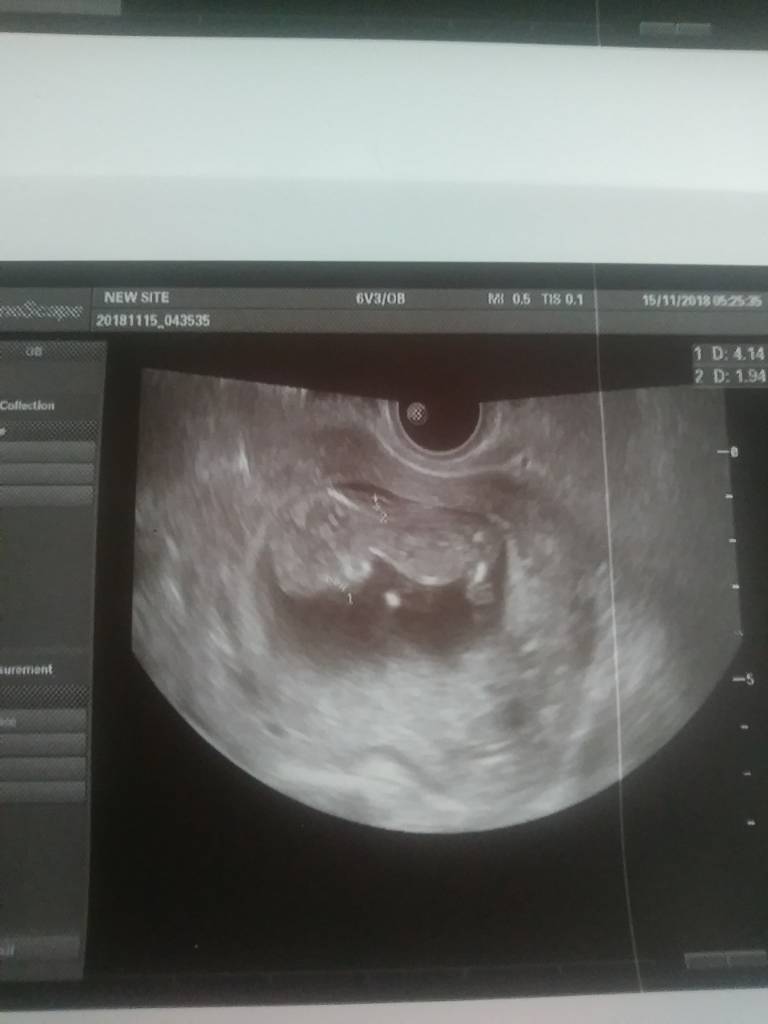

Czerwcowe Mamy 2019

Moje maleństwo ma 53.03 mm. Pani gin dałam posłuchać serduszka 156 na min. Widziałam jak macha nóżkami i rączkami. Nie chciała nic sugerować bo to za wcześnie jeszcze ale na jej oko to chłopiec, ale oczywiście mam sie nie sugerować. 22.11 mam prenatalne i może wtedy coś powiedzą. A i myślałam, że bede miała usg przez brzuch ale bylo kiepsko widać, wiec miałam dopochwowe jeszcze.